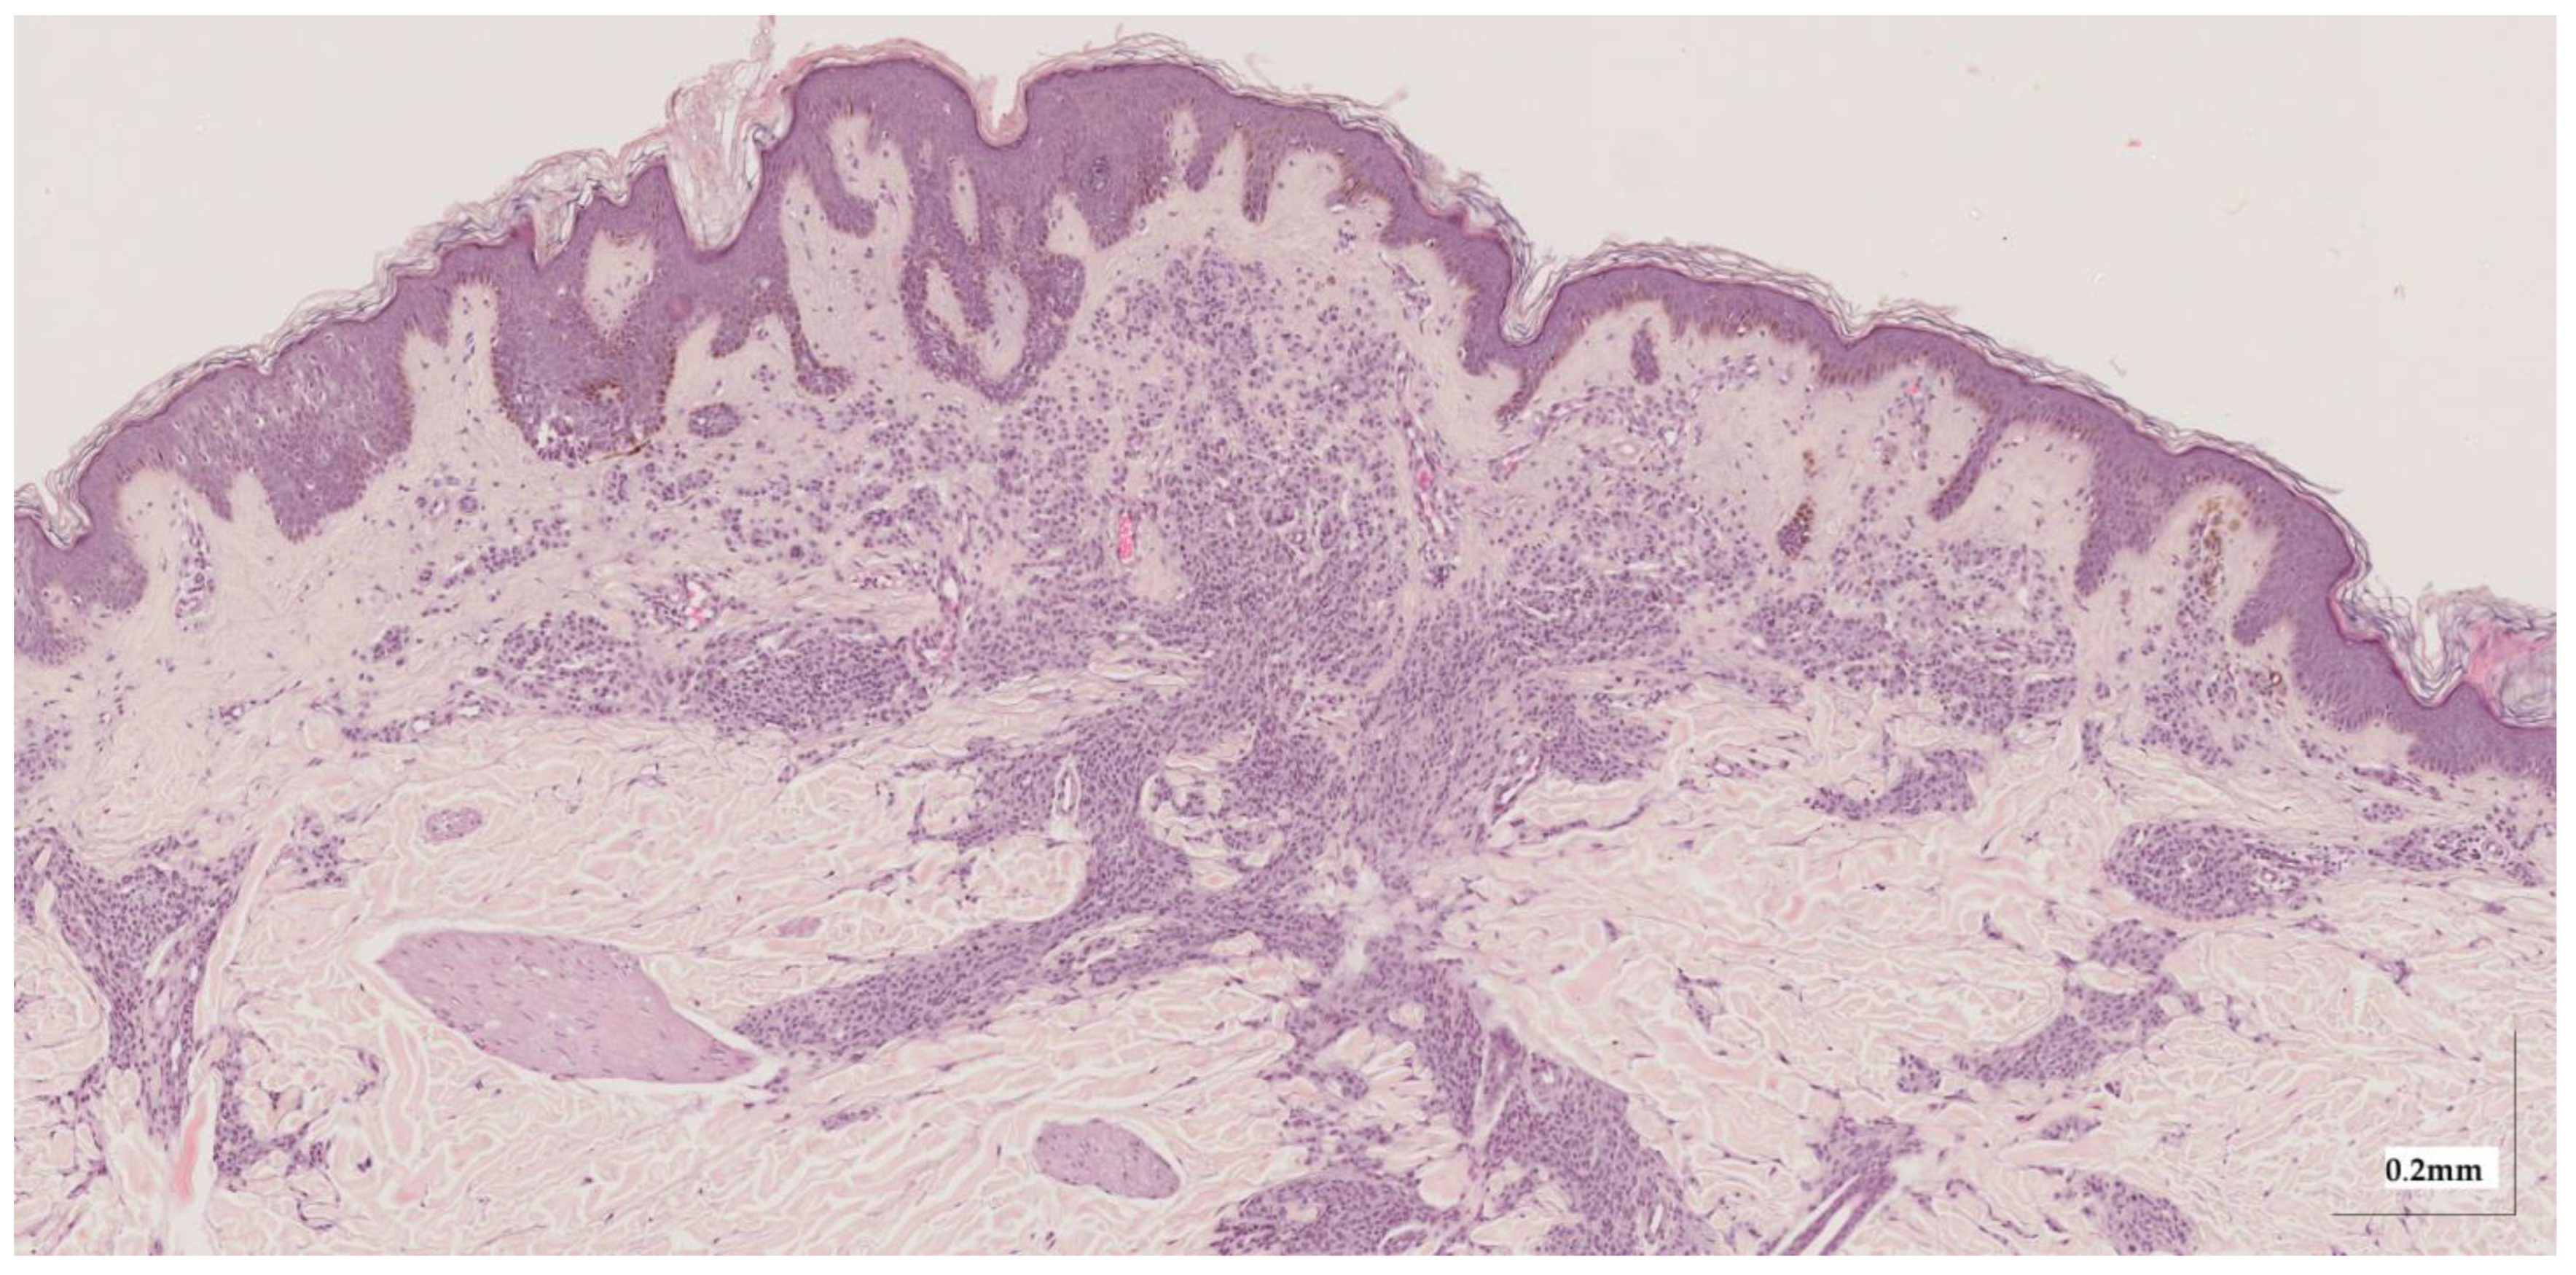

| Superficial spreading melanoma (SSM) Case 1 | Localization: right anterior arm |

![]() | ![]() |